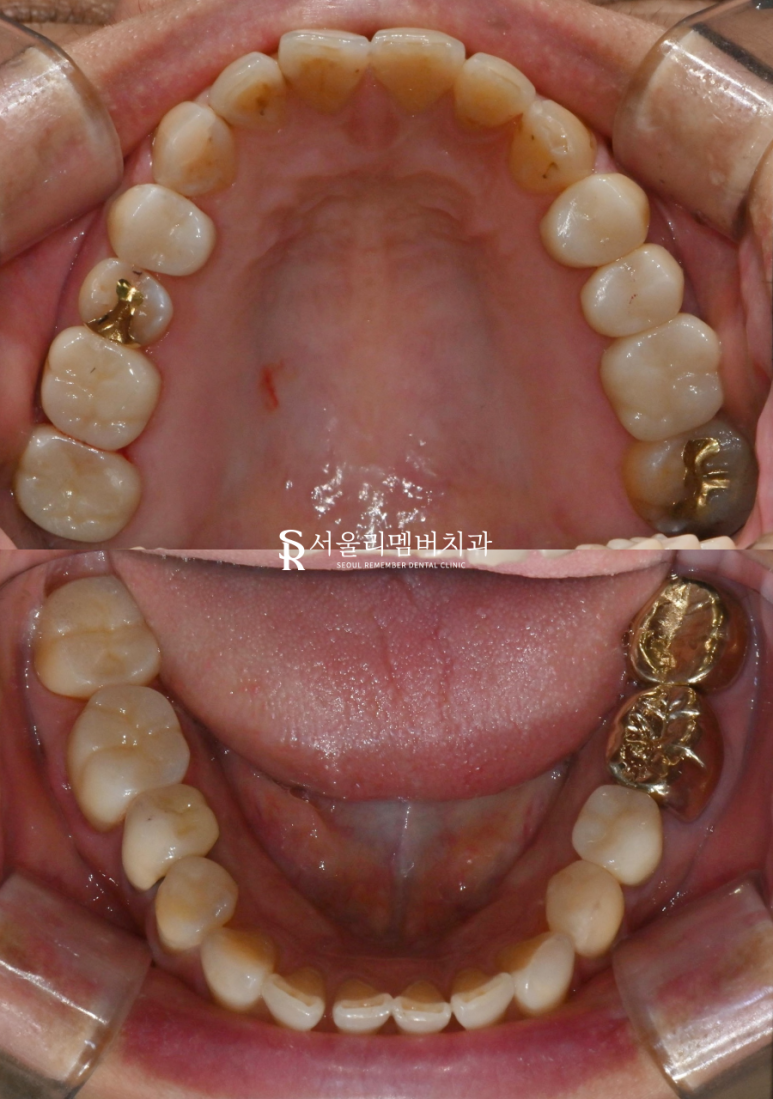

구내사진

곳곳에 심한 충치들을 확인할 수 있습니다.

어금니 쪽도 새로 만들어진

지크로니아 크라운으로

심미적으로 조화롭게

치료가 끝납니다.

앞니 심미 레진 치료와

어금니 지르코니아 크라운치료 모두

마무리 됩니다.